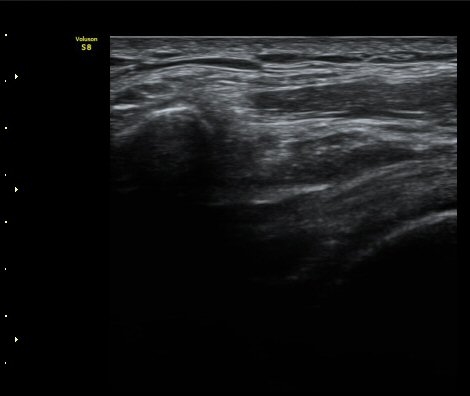

Áõ·Ê 2)

°ßºÀ¿À±¸µ¹±âÀδë Á¾´Ü¸é°Ë»ç¿¡¼­ ÀδëÀÇ ¿ÜÃø¿¡ ±¹¼ÒÀûÀÎ ÀÎ?ºñÈİ¡ °üÂûµÈ´Ù(»çÁø 3).

±Ø»ó°Ç Á¾´Ü¸é°Ë»ç½Ã ±Ø»ó°ÇÀÇ Ç¥Ãþ¿¡¼­ °üÂûµÇ´Â °ßºÀ¿À±¸µ¹±â Ⱦ´Ü¸é°Ë»ç»ó¿¡¼­

ÀδëÀÇ ºñÈİ¡ °üÂûµÈ´Ù(»çÁø 4). ±Ø»ê°ÇÀÇ Á¾´Ü¸é°Ë»ç¿Í Ⱦ´Ü¸é°Ë»ç¿¡¼­ ±Ø»ê°Ç ½ÉÃþ¿¡

Àú¿¡ÄÚ º´º¯ÀÌ °üÂûµÈ´Ù(»çÁø 5, 6).